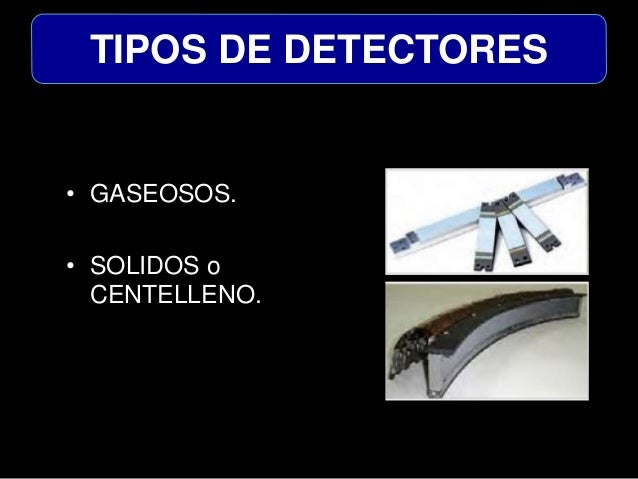

DETECTORES